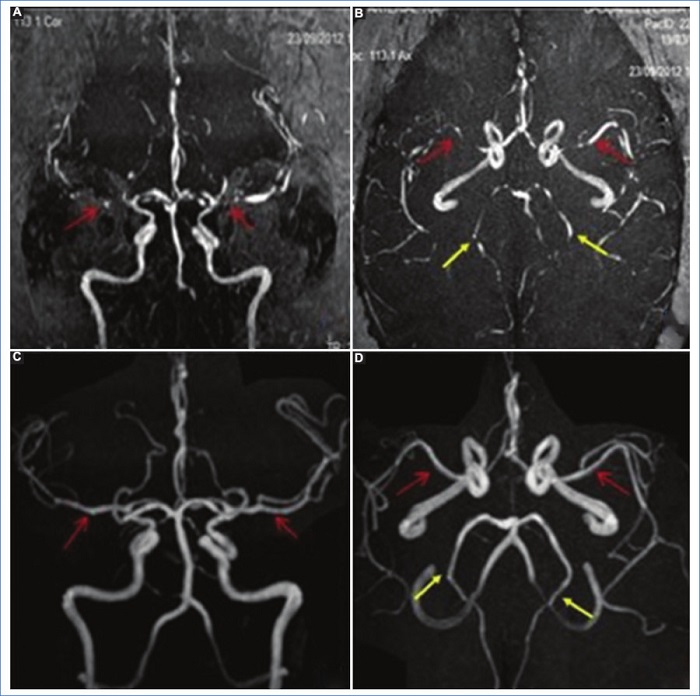

Signos directos: en los senos venosos se evidencian defectos de flujo que se traducen en alteración de la señal (Fig. 4). La intensidad de señal del trombo es similar a la evolución de la sangre en un hematoma18:

Trombo agudo (1-5 días): la desoxihemoglobina es la molécula dominante. El coágulo es isointenso en T1, hipointenso en T2 y marcadamente hipointenso en GRE (esto puede simular un vacío de flujo)18,19.

Trombo subagudo temprano (entre los días 6 y 15): se produce la oxidación de la molécula de desoxihemoglobina a metahemoglobina. El coágulo es hiperintenso en las secuencias T1 y T218,19.

Trombo subagudo tardío (> 15 días): continúa la desintegración de la molécula de hemoglobina. Esta etapa puede ser un reto, ya que la trombosis crónica muestra una recanalización parcial y la señal del coágulo es iso-hiperintensa en T2 e isointensa en T12,18.

Trombo crónico (> 30 días): el trombo es isointenso o hiperintenso en T2 e hipointenso en T1. Se ha observado que, luego del contraste, a veces, el seno presenta un realce similar al del seno normal, probablemente vinculado a la organización del trombo con signos de vascularización intrínseca18,19,20.

Signos indirectos: los hallazgos en la RM son los mismos que en la TC, aunque más sensibles y específicos. Comprenden el infarto venoso que coexiste con edema cerebral vasogénico o citotóxico con o sin hemorragia intraparenquimatosa (Fig. 5) 18,19,20.

RM con secuencias vasculares sin contraste: es útil no solo para la documentación del trombo, sino también para el seguimiento de la recanalización postratamiento. Esta técnica suele usarse en las gestantes y en pacientes con falla renal, para evitar la administración de contraste paramagnético. Se realiza usando la secuencia Phase contrast, la cual es sensible a los flujos lentos y permite obtener imágenes con mayor resolución18,19,20.

RM con secuencias vasculares con contraste: si tras la realización de las secuencias sin contraste persiste la duda diagnóstica, es necesario administrar contraste paramagnético para diferenciar la trombosis venosa de un flujo vascular lento. Al igual que en la TC, se visualizará un defecto de relleno a nivel del seno venoso afectado18,19,20.